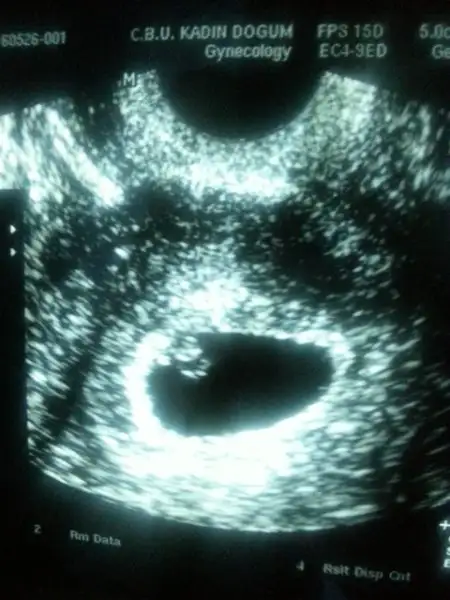

6+0 vajinal 8+0 karından 8+2 vajinal

Eki Görüntüle 1847341 bu bebegimin 9 haftalik usg resimi... :) burda ne gibi?